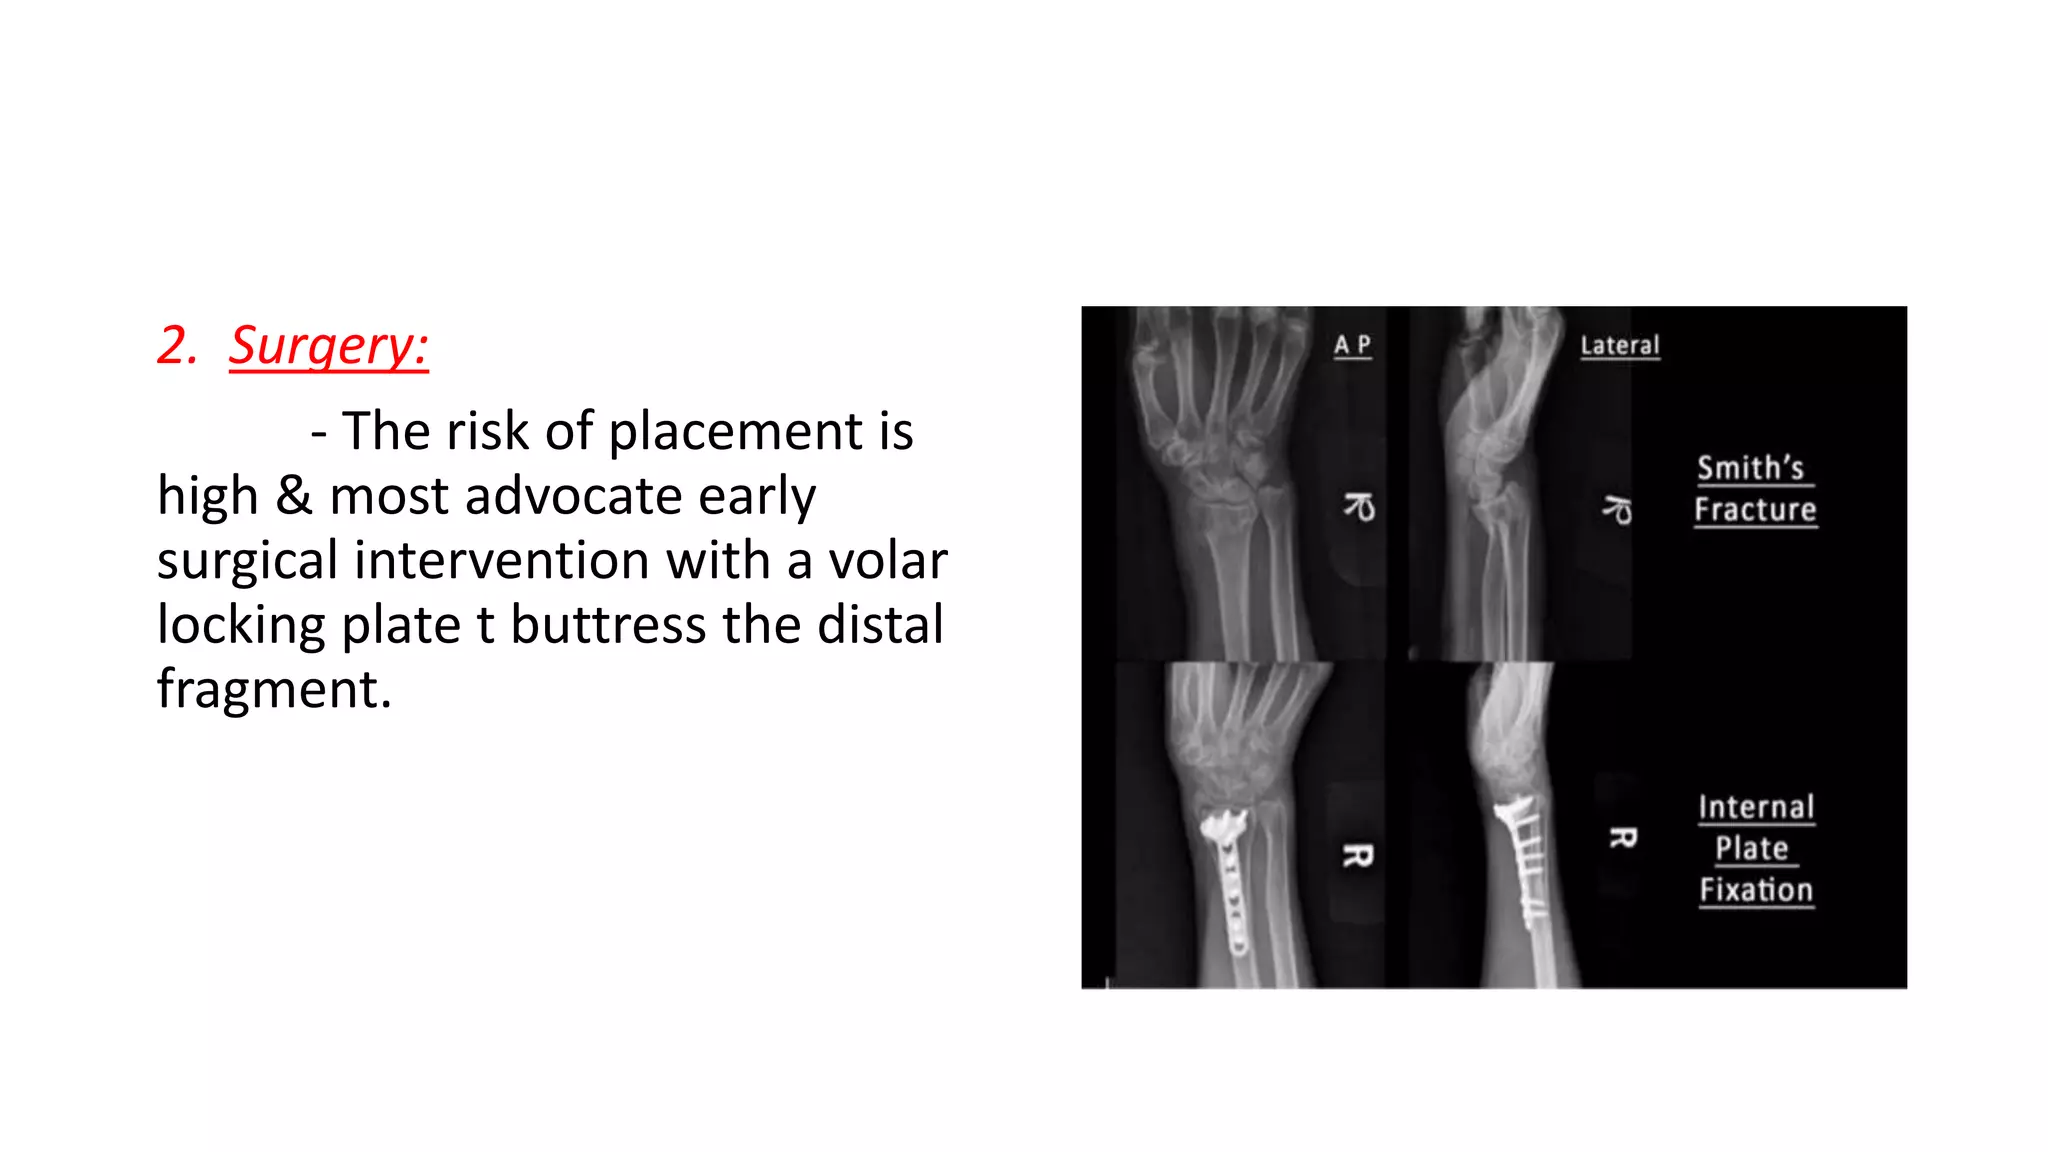

2. Surgery:

- The risk of placement is

high & most advocate early

surgical intervention with a volar

locking plate t buttress the distal

fragment.

- There is # through the distal radial metaphysis.

- A lateral view shows that the distal fragment is

displaced or tilted anteriorly.